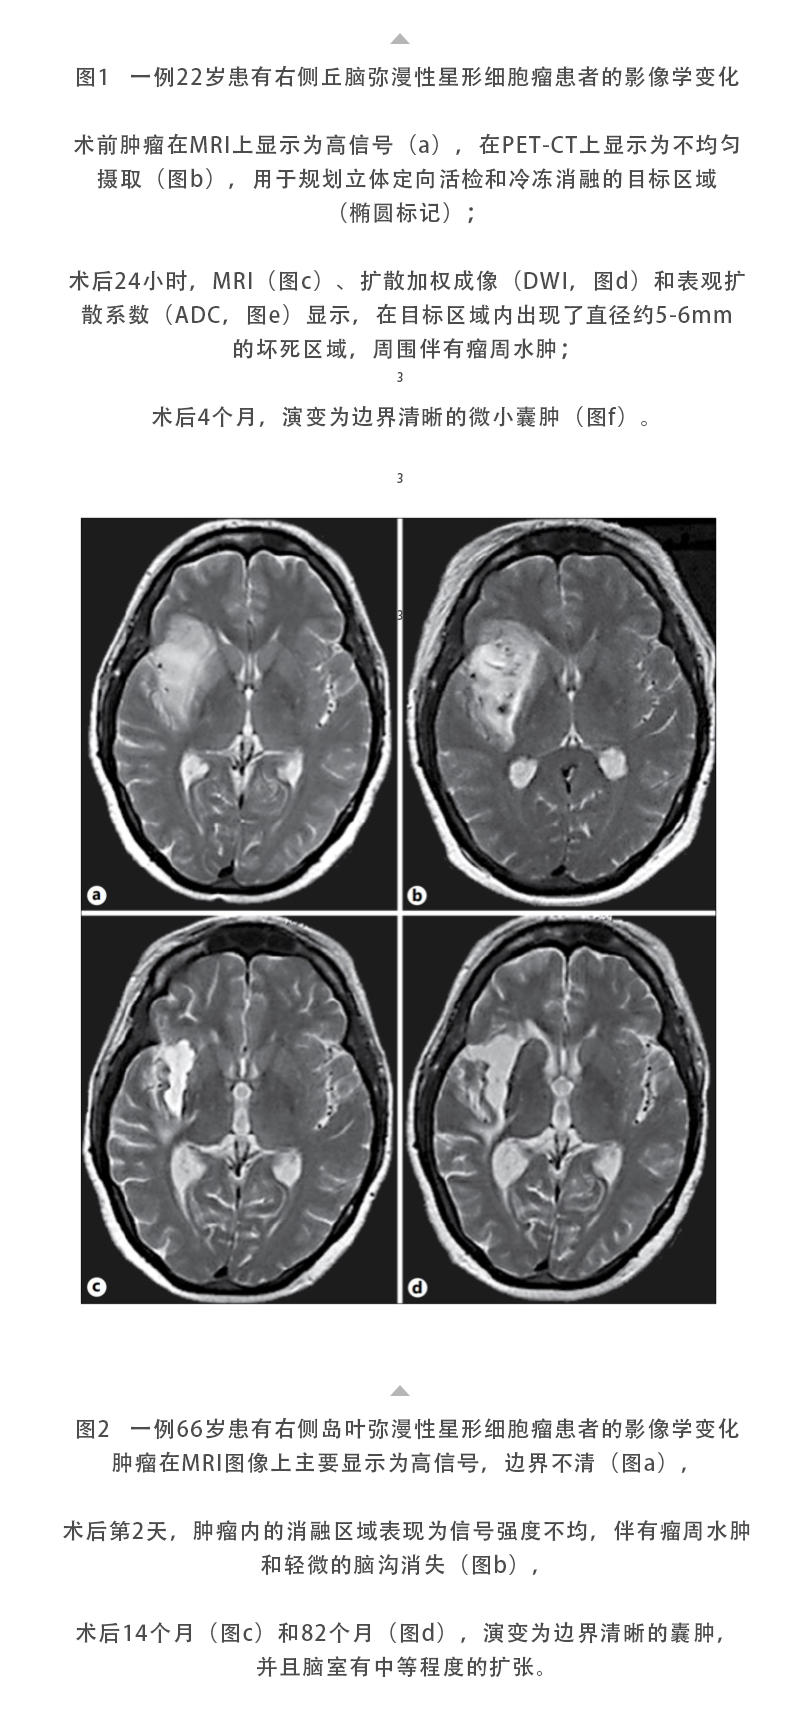

日本特黄特色a大片免费高清观看视频_亚洲午夜综合_一女被两男3p做爰视频_丰满少妇久久_欧美激情在线第一页_久久五月激情_亚洲成人激情在线_滚床单又黄又肉细节描写_日韩av综合在线观看_人妖一级片